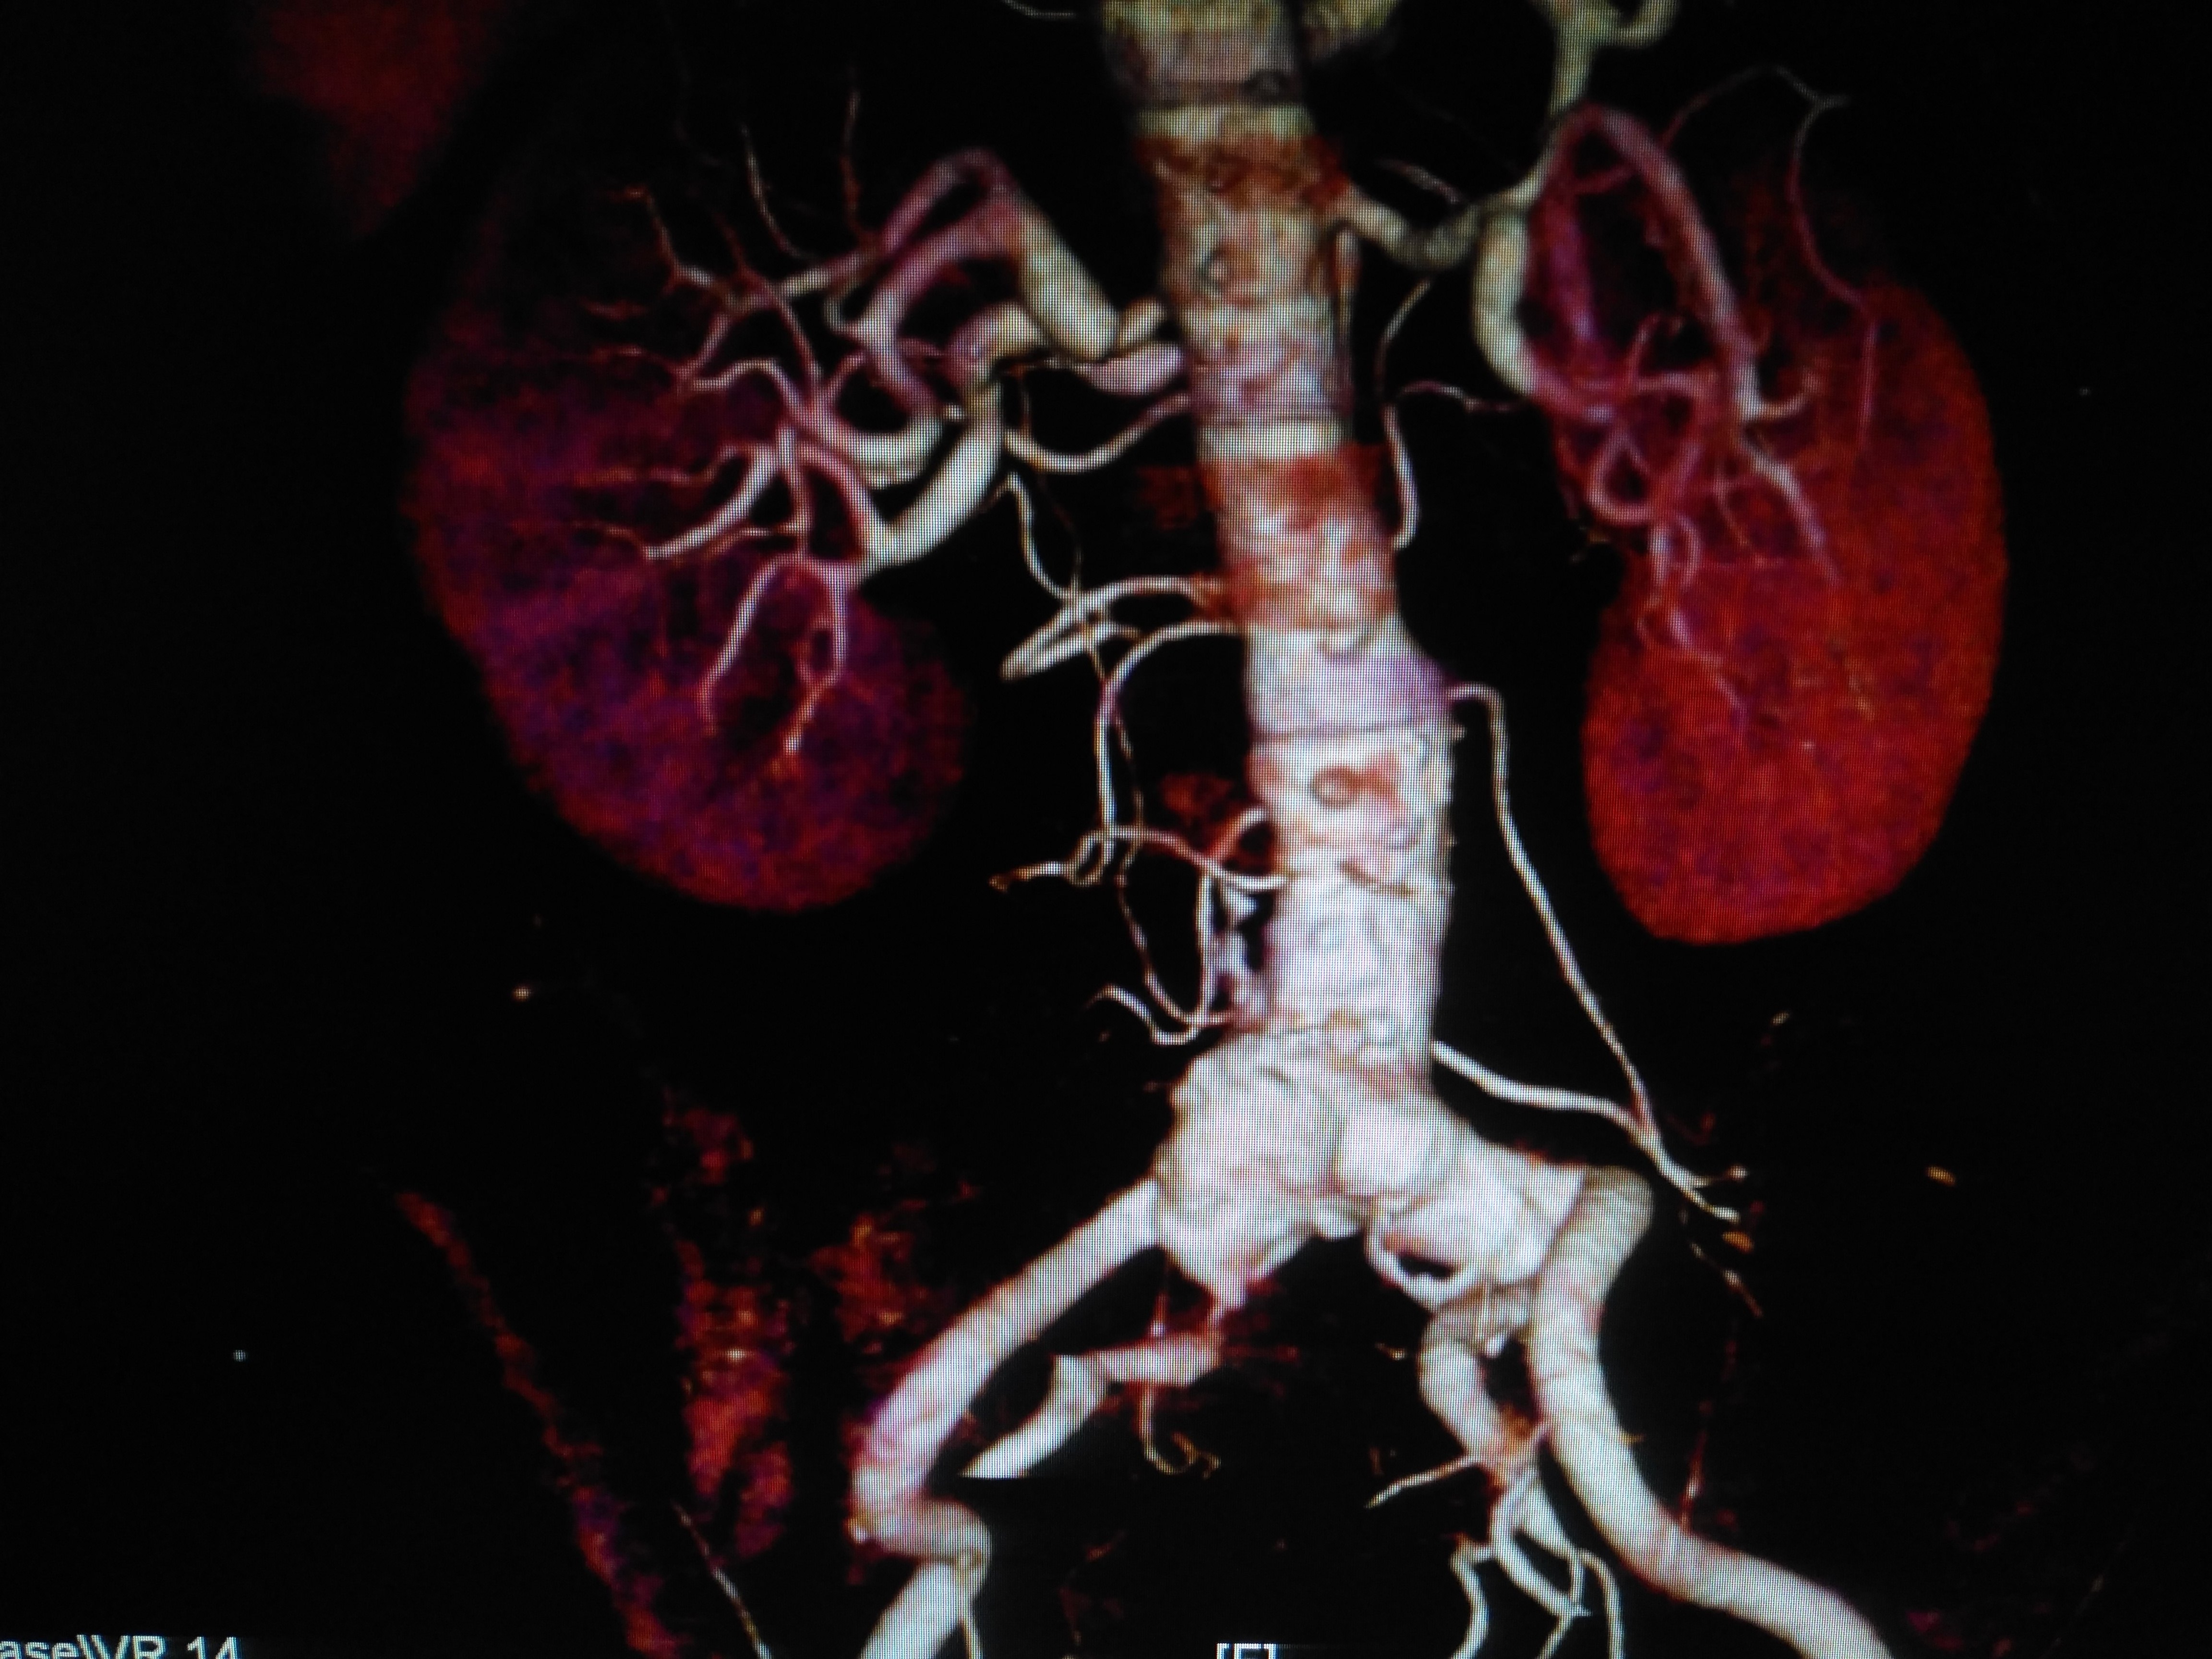

图1-术前ct评估,肾下腹主动脉瘤,右髂内开口狭窄,左髂内动脉开口距离